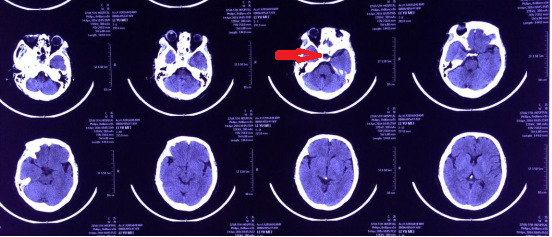

手术非常成功,在切除肿瘤的同时,完好地保护了王女士的视神经、下丘脑、颅底动脉等重要结构。术后第2天,王女士即能下地行走,视力也得到明显改善,视野较术前扩大,头痛乏力的症状也消失了。没有出现其他并发症,一周后即康复出院,复查头颅CT肿瘤切除满意(图5)。

图5